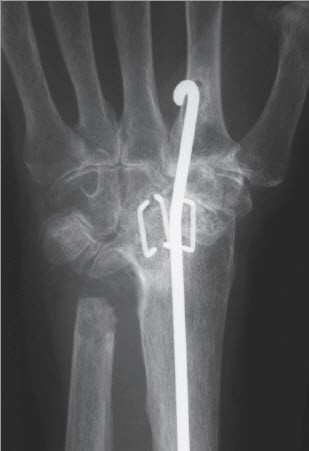

Bei einer isolierten Arthrose des unteren Speichen-Ellen-Gelenks (DRUG) findet sich vor allem eine schmerzhafte und eingeschränkte Vorderarm-Rotation. Die Beugung und Streckung im Handgelenk ist nicht oder nur minimal betroffen. In diesen Fällen wird eine isolierte Teilversteifung des Gelenkes nach Sauvé- Kapandji durchgeführt (Abb. 2). Bei diesem Eingriff wird das Ellenköpfchen mit der Speiche verbunden. Um die Vorderarm- Drehbewegung gleichwohl erhalten zu können, ist es erforderlich, ein Knochenstück der Elle herauszunehmen. Dieser Eingriff hat sich bewährt in Fällen, in denen das Gelenk isoliert zerstört worden ist. Eine solche Zerstörung kommt bei gewissen Formen der chronischen Polyarthritis vor, ferner auch als Folge von Speichenbrüchen.

Das Ellenköpfchen wird meistens mit einer Schraube zur Speiche fixiert. Diese Fixation ist nur bedingt übungsstabil, weshalb eine zusätzliche äussere Fixation in Form einer abnehmbaren Schiene erforderlich ist. Nach der Operation bleiben sowohl die Handgelenkbeweglichkeit als auch die Unterarm-Rotation in der Regel erhalten.